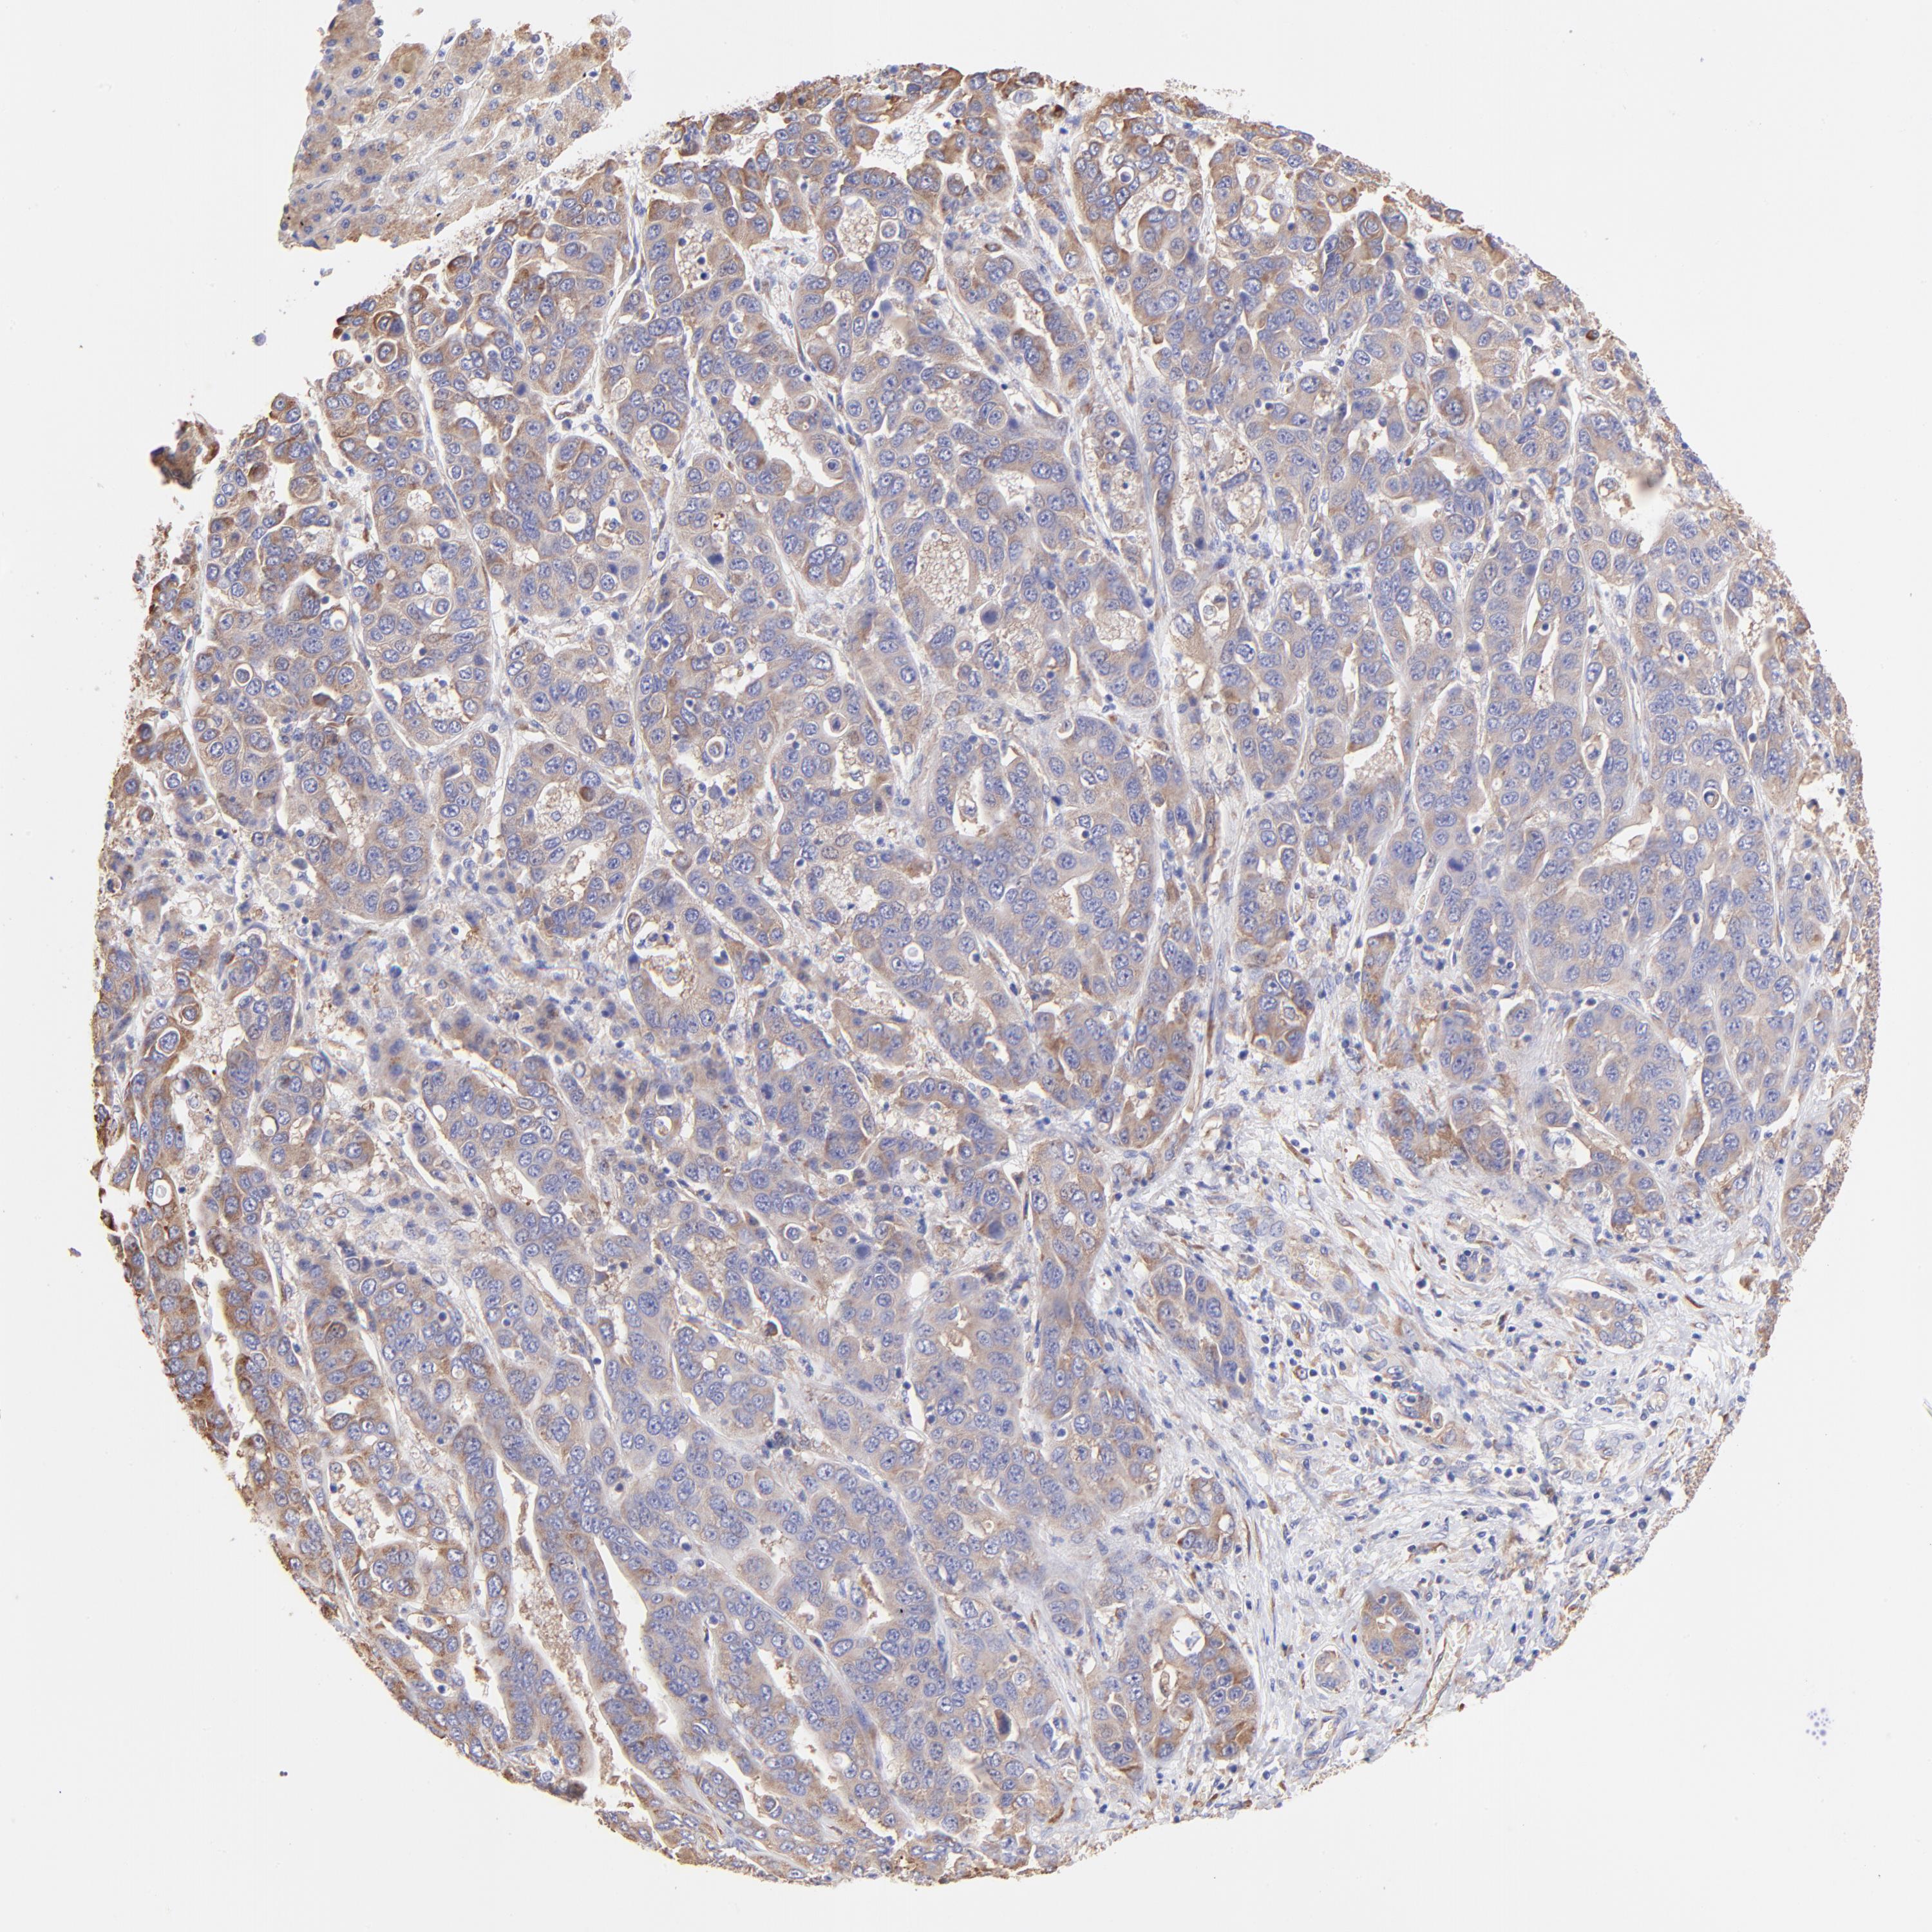

LIVER CANCER - Protein expressioni

A mouse-over function shows sample information and annotation data. Click on an image to view it in a full screen mode. Samples can be filtered based on level of antibody staining by selecting one or several of the following categories: high, medium, low and not detected. The assay and annotation is described here.

Note that samples used for immunohistochemistry by the Human Protein Atlas do not correspond to samples in the TCGA dataset.

Antibody stainingi

Antibody staining in the annotated cell types in the current human tissue is reported as not detected, low, medium, or high, based on conventional immunohistochemistry profiling in selected tissues. This score is based on the combination of the staining intensity and fraction of stained cells.

Each image is clickable and will lead to virtual microscopy that enables deeper exploration of all samples and also displays staining intensity scores, fraction scores and subcellular localization as well as patient and tissue information for each sample.

Antibody HPA002651

Staining

High

Medium

Low

Not detected

Intensity

Strong

Moderate

Weak

Negative

Quantity

>75%

75%-25%

<25%

None

Location

Nuclear

Cytoplasmic/membranous

Cytoplasmic/membranous,nuclear

Cholangiocarcinoma

Carcinoma, Hepatocellular, NOS